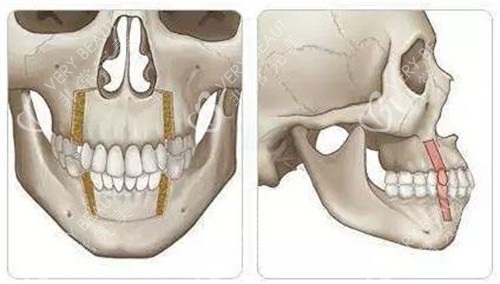

何医生团队用三维CT和咬合模型分析我的骨骼问题,明确告诉我:“单纯正畸改善有限,双鄂截骨才能让上下颌骨回归正确位置。”

先确诊再行动——找正规颌面医生判断是否需要手术;